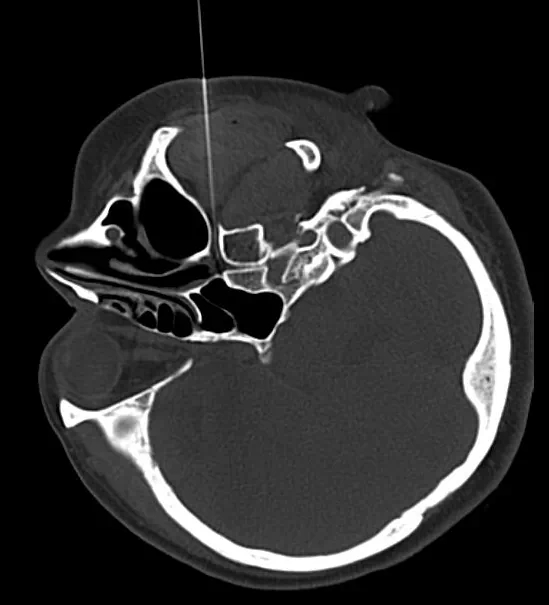

过敏性鼻炎是一种常见病和多发病,主要是由过敏物质,如花粉,雾霾,灰尘,异体蛋白,甚至是空气质量和温度引起的。有的根本就查不到过敏源,其症状有鼻塞,鼻痒,流涕,打喷嚏。更有甚者晚上睡觉只能张口呼吸,严重影响睡眠质量。所以,它对人们的日常生活影响巨大,且常影响你的公众社交形象!赵女士就是一位患此病二十多年的患者,用她自己的话说这么多年来医院没少去,药没少吃,罪没少受,但就是效果不大。终于一次偶然的机会,经朋友介绍,她找到了世界中医药联合会疼痛与康复委员会常务理事,副主任医师梁文军医生,采用国际先进技术一一CT引导下蝶腭神经节脉冲治疗过敏性鼻炎。赵女士半信半疑地在梁主任确保治疗安全的前提下接受治疗。真是医治有缘人,赵女士在CT引导下大概45分钟基本无任何痛苦就结束了治疗。赵女士现在症状基本消失,只是偶尔过度疲劳或感冒后还有些许症状,咨询了梁大夫说大概还要3~6个月的恢复期。

梁医生师从于北京中日友好医院杨克勤教授,而杨教授早年东渡日本,主要从事三叉神经痛,癌症痛,顽固性头痛,颈肩腰腿痛,带状疱疹痛及过敏性鼻炎的病因研究和治疗!而蝶腭神经节正是支配鼻粘膜的主要神经,当鼻粘膜受到过敏源刺激后,交感神经兴奋,使鼻粘膜充血水肿,导致流涕,鼻塞,鼻痒,打喷嚏,甚至呼吸困难!而蝶腭神经节的治疗既不影响嗅丝,又不会导致鼻腔干燥而产生空鼻症!这是手术有创治疗无法避免的!在杨教授和梁医生亲手诊治的上千例患者中,显效率在95%以上。